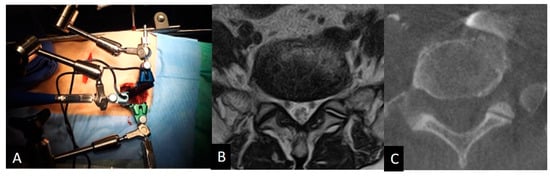

On MRI axial scan at either the caudal L5 endplate level or the cephalad S1 endplate level, the distance from the sagittal mid-vertebral line to border of the right and left common iliac vessels was measured as (L5-LCIV, L5-RCIV, L5-LCIA, L5-RCIA, S1-LCIV, S1-RCIV, S1-LCIA, S1-RCIA) (Figure 2). The vascular window was measured between right and left iliac vessels, expressed as the central corridor window (CCW). The lateral corridor window was expressed as the distance between the lateral border of the left common iliac vein and medial border of psoas muscle (LCW) (Figure 2). Iliolumbar vein anatomy was also evaluated in terms of the visualization rate (%), the axial position from the sagittal mid-vertebral line (L5-ILV, S1-ILV). The type of iliolumbar vein was classified according to Nalbandian et al. [6] (Figure 3). Type 0 refers to no ILV, type 1 is the single variant. Multiple ILVs are categorized into types 2, 3, and 4 according to the number of veins found. The vertical position of common iliac vein bifurcation was measured from the lower endplate of L5 (Figure 4). For precise measurements, all imaging data were transferred to the three-dimensional image analysis system (Synapse Vincent, FujiFilm, Co., Tokyo, Japan), and the measurements were performed on its workstation.

The intraoperative vein anatomy in the right decubitus position was evaluated with vein-enhanced intraoperative CT (O-armO2, Medtronics) (Figure 1C). Prior to the incision made for OLIF51 surgery, the contrast medium was injected from the peripheral vein of left foot, and a O-arm 3D scan was subsequently taken. The axial and sagittal positions of the vein structure surrounding the L5/S1 disc were measured according to the same parameters as those in the supine position on MRI (Figure 2). The vein position on intraoperative CT was subsequently compared to that in the supine position on MRI, and the movement of the vein structure was quantitatively analyzed (Figure 2 and Figure 4).

Figure 2. Measurement of the vascular position at the L5/S1 disc level. The distance from the midline of the disc to each vascular tissue was measured either counterclockwise (minus) or clockwise (plus). RCIA: right common iliac artery; RCIV: right common iliac vein; LCIA: left common iliac artery; LCIV: left common iliac vein; Psoas: iliopsoas muscle.